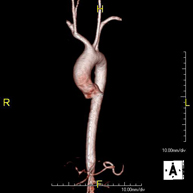

Prova diagnòstica no invasiva que consisteix en l'obtenció d'imatges d'alta definició anatòmica de tot el cos mitjançant l'ús d'un camp electromagnètic i ones de ràdio (amb un emissor i un receptor). No utilitza radiació ionitzant. És una prova molt important en la recerca de metàstasi en pacients amb neoplàsia coneguda. No requereix preparació prèvia. No és necessari l'ús de contrast paramagnètic (Gadolini). - Angio RM d'Aorta-ilíaca

Prova diagnòstica no invasiva que consisteix en l'estudi de l'artèria aorta abdominal i de les artèries ilíaques, amb l'obtenció d'imatges d'alta definició anatòmica mitjançant l'ús d'un camp electromagnètic i ones de ràdio (amb un emissor i un receptor). És indispensable l'ús de contrast paramagnètic (Gadolini). No utilitza radiació ionitzant. La qualitat de les imatges permet realitzar reconstruccions en 2D i 3D. Aquesta prova està especialment indicada com a estudi prequirúrgic (mapa vascular) abans d'intervencions percutànies o quirúrgiques d'aorta abdominal i artèries ilíaques, per a l'estudi complementari en pacients amb isquèmia de membres inferiors, etc. - Angio RM Arterial d'extremitats inferiors

Prova diagnòstica no invasiva que consisteix en l'estudi vascular del sector aorto-ilíac i dels vasos arterials de les dues extremitats inferiors, am l'obtenció d'imatges d'alta definició anatòmica mitjançant l'ús d'un camp electromagnètic i ones de ràdio (amb un emissor i un receptor). És indispensable l'ús de contrast paramagnètic (Gadolini). No obstant, no utilitza radiació ionitzant. La qualitat de les imatges permet realitzar reconstruccions en 2D i 3D. Està especialment indicat en aquells pacients en els que hi ha sospita de malaltia vascular a les dues extremitats, en pacients amb malaltia vascular de les dues extremitats com a mapa vascular abans del tractament (percutani o quirúrgic), com a mapa vascular prequirúrgic en pacients amb lesions òssies o musculars que requereixin cirurgia, etc. - Angio-RM d'Artèries renals

Prova diagnòstica no invasiva que consisteix en l'obtenció d'imatges d'alta definició anatòmica de l'aorta toràcica (principal artèria del tòrax) mitjançant l'ús d'un camp electromagnètic i ones de ràdio (amb un emissor i un receptor). No utilitza radiació ionitzant. En la majoria dels casos és necessari l'ús de contrast paramagnètic (Gadolini). Permet un estudi angiogràfic no invasiu gràcies a la injecció de Gadolini amb posterior reconstrucció en 2D i 3D, mitjançant estacions de treball especialitzades. També inclou l'estudi de la vàlvula aòrtica, informació imprescindible en el cas que el pacient necessiti cirurgia. Aquesta prova està especialment indicada en pacients que requereixen tractament quirúrgic (com a mapa vascular prequirúrgic), en el seguiment de pacients amb aneurismes d'aorta, etc. - Angio-RM d'Aorta Abdominal

Prova diagnòstica no invasiva que consisteix en l'estudi de l'artèria aorta abdominal per obtenir imatges d'alta definició anatòmica mitjançant l'ús d'un camp electromagnètic i ones de ràdio (amb un emissor i un receptor). És indispensable l'ús de contrast intravenós paramagnètic (Gadolini). No obstant, no utilitza radiació ionitzant. La qualitat de les imatges permet realitzar reconstruccions en 2D i 3D. Està indicat en aquells pacients amb malaltia vascular (Aterosclerosi), per a l'estudi d'aneurismes, en estudis prequirúrgics de lesions adjacents a l'aorta abdominal com "mapa" vascular, etc. - Angio-RM Aorta ilíaca

Prova diagnòstica no invasiva que consisteix en l'estudi de l'artèria aorta abdominal per obtenir imatges d'alta definició anatòmica mitjançant l'ús d'un camp electromagnètic i ones de ràdio (amb un emissor i un receptor). És indispensable l'ús de contrast intravenós paramagnètic (Gadolini). No obstant, no utilitza radiació ionitzant. La qualitat de les imatges permet realitzar reconstruccions en 2D i 3D. Aquesta prova està especialment indicada com estudi prequirúrgic (mapa vascular) abans d'intervencions percutànies o quirúrgiques d'aorta abdominal, per a l'estudi complementari en pacients amb isquèmia de membres inferiors, etc. - Angio-RM d'Artèries renals